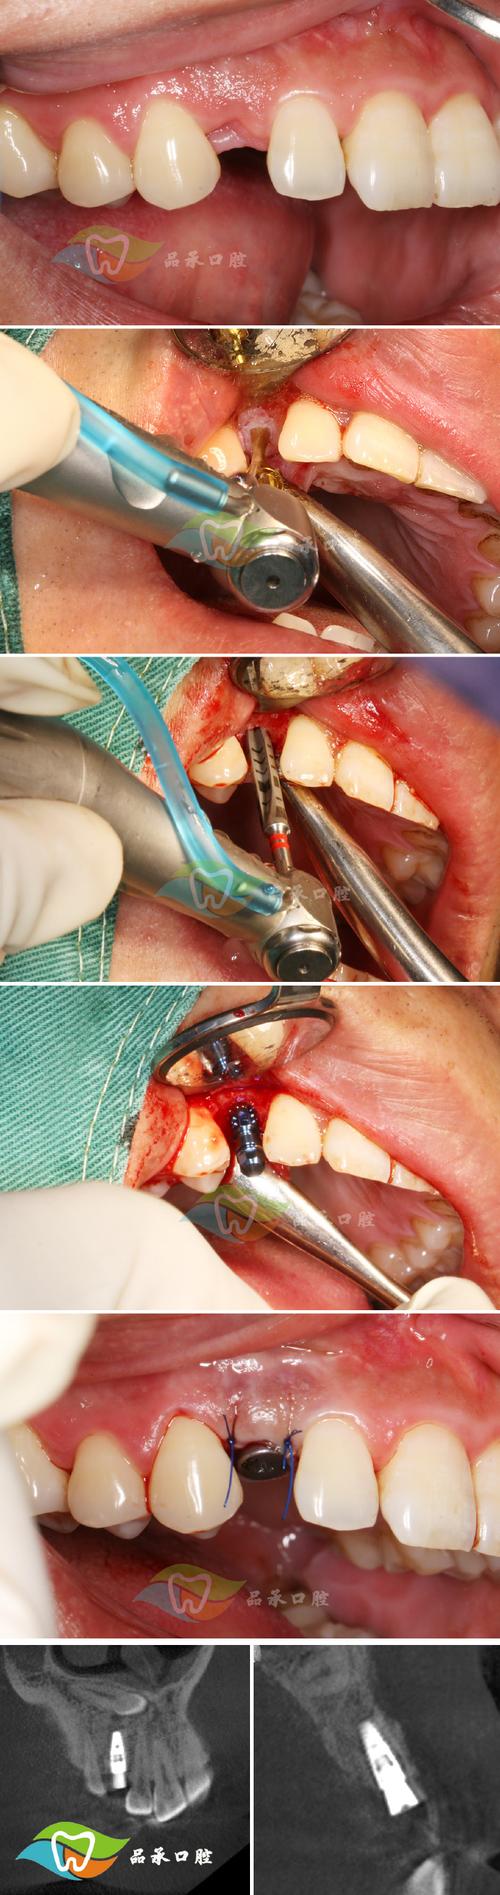

植骨后缝线的主要作用是固定骨粉颗粒、封闭创口、防止细菌侵入,并为组织愈合提供临时支撑,临床常用的缝线分为可吸收线和不可吸收线:可吸收线(如胶原蛋白线、聚乳酸线)在体内会被酶分解,通常术后1-2周逐渐脱落;不可吸收线(如丝线、尼龙线)需医生在术后7-10拆除,若自行脱落则可能存在异常,缝线脱落的时间与材质、伤口张力、个体愈合速度相关,多数患者可在术后5-14天见到缝线丝线松动、脱落,这是组织愈合的标志,无需过度紧张。

但若缝线在术后3天内脱落,或伴随伤口明显异常,则需警惕异常情况,常见原因包括:①咀嚼不当:过早用患侧咬硬物,导致缝线受力脱落;②口腔卫生不佳:食物残渣堆积引发感染,导致伤口裂开、缝线脱落;③外力碰撞:意外磕碰使伤口受力增大;④骨粉排异:少数患者对骨粉材料敏感,出现局部炎症反应,影响缝线固定;⑤缝合技术问题:若术中缝合过松、对位不良,也可能导致缝线提前脱落,异常脱落的伴随症状通常包括伤口持续性出血、红肿加剧、流脓、异味,甚至骨粉暴露,这些情况可能提示感染或愈合不良,需及时干预。

缝线脱落后的护理是保障植骨效果的关键,保持口腔清洁:术后24小时内可轻柔漱口(遵医嘱用淡盐水或氯己定漱口液),避免用力刷牙或触碰植骨区;24小时后可正常刷牙,但需避开植骨区域,使用软毛牙刷,饮食调整:以温凉、软质食物为主(如粥、酸奶、蒸蛋),避免过热、过硬、辛辣刺激性食物,防止伤口刺激;戒烟戒酒,减少尼古醇和酒精对愈合的影响,观察伤口状态:每日检查伤口是否有红肿、渗液、骨粉暴露,若出现轻微渗血,可用无菌棉球轻压止血;若渗血持续或流脓,需立即就医,遵医嘱用药:术后常规使用抗生素(如阿莫西林)预防感染,服用止痛药(如布洛芬)缓解疼痛,需按时按量服用,不可擅自停药。